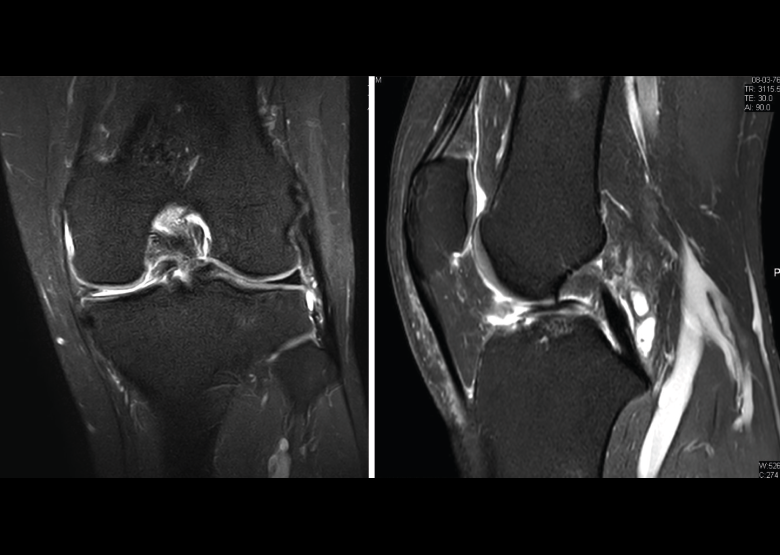

Figura 35. Corte de secuencia coronal y sagital de resonancia magnética de rodilla: rotura en asa de cubo del menisco interno con fragmento desplazado al intercóndilo.

4.3. Osteocondritis

En la osteocondritis se aprecia una lesión subcondral caracterizada por resorción ósea, colapso y la formación de un secuestro.

El estudio por RM es una herramienta valiosa para diagnosticar e identificar las lesiones del cartílago. Conocer el aspecto del cartílago y saber cuánto y cuándo se lesiona, basándose en las clasificaciones actuales, permiten al radiólogo proporcionar la máxima información al clínico(20).

Figura 53. Corte de secuencia sagital (A) y axial (B) T2 Fat-Sat de RM de rodilla: lesiones osteocondrales en el fémur y la rótula.

Numerosos estudios demuestran la utilidad de la RM para definir la estabilidad o inestabilidad de la lesión en la osteocondritis, destacando su carácter no invasivo y la capacidad de valorar la progresión y la respuesta al tratamiento(21)(Figuras 53 y 54).

Figura 54. Corte de secuencia T1 y T2 Fat-Sat coronal de resonancia magnética: gran osteocondritis en el cóndilo femoral interno con edema en la medular adyacente.